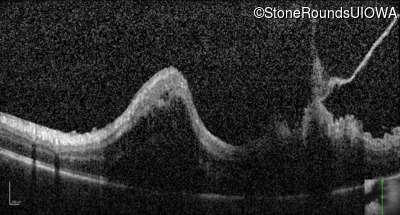

Optical Coherence Tomography - Right - Hand Motion

Exemplar / OCT Stack

OCT Stack